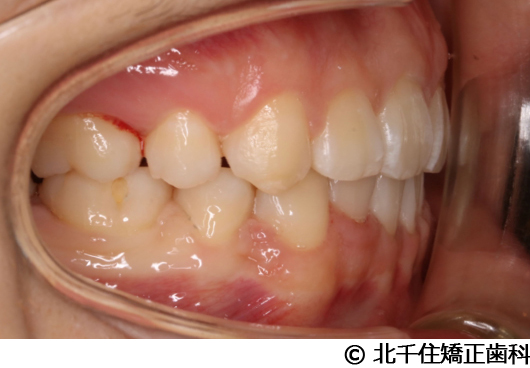

【症例3】叢生

- 治療前

- 治療後

- 治療名

- 叢生

- 費用

- 1,125,000円(税込)

- 期間

- 2年1ヵ月

- 治療回数

- 26回

- 通院頻度

- 1ヵ月ごと

- 年齢・性別

- 19歳3ヵ月・女性(初診時)

治療内容

主訴:デコボコ、口元の突出

上下顎第一小臼歯4本を抜歯してワイヤー矯正(セラミックブラケット)。

叢生に対し抜歯を併用した矯正治療により、歯列および咬合関係の調整を行った症例である。治療後は保定装置を使用し、歯列および咬合の安定維持を目的として定期的な経過観察を行っている。

※治療結果は個人差があります。

治療を行う上での注意点(リスク・副作用)

歯磨き不良に伴うカリエスや歯周病、歯根吸収など。